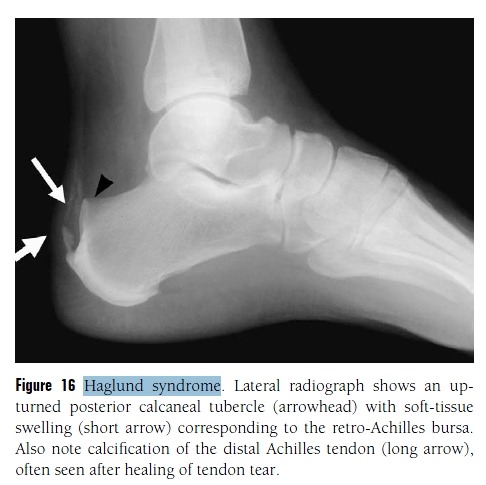

Calcaneonavicular Coalition

Figure 19 Coalition.

(A) Calcaneonavicular coalition. Lateral view of the ankle shows a talar beak (arrow), which is often

associated with coalition. Note the “anteater sign,” in which the anterior calcaneal process (arrowheads) continues into

the navicular bone, caused by a coalition.

(B) Calcaneonavicular coalition. Lateral oblique view of the foot of the same patient as (A) optimally depicts the site of calcaneonavicular coalition (arrows).

(C) Subtalar coalition. Lateral view of the ankle shows a talar beak (arrow) and a “C sign” (arrowheads) caused by a prominent sustentaculum tali seen in the setting of subtalar coalition

(D) Subtalar coalition. Harris–Beath view of the same patient as (C) shows bone prominence at the sustentaculum tali (arrow) and lack of visualization of the middle facet compared with the posterior facet (arrowhead), which should be in the same plane.